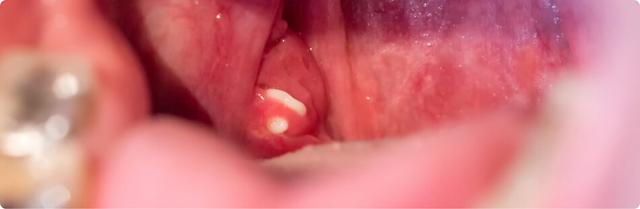

Mandelsteine, auch Tonsillensteine oder Tonsillolithen genannt, entstehen in den Gaumenmandeln (Tonsillen). Diese kleinen weiß-gelblichen Gebilde bilden sich in den tiefen Krypten der Mandeln. Sie bestehen aus abgeschilferten Zellen, weißen Blutkörperchen, Bakterien und Speiseresten. Mandelsteine sind etwa drei bis vier Millimeter groß und können verschiedene Konsistenzen haben, von weich über krümelig bis steinhart.

Mandelsteine können oft unbemerkt bleiben, es sei denn, sie verursachen Beschwerden wie Mundgeruch oder Schluckbeschwerden. Sie sehen aus wie kleine Klumpen und haben eine Größe von etwa drei bis vier Millimetern. Es ist wichtig zu beachten, dass Mandelsteine nicht mit den weißen Stippen einer akuten Mandelentzündung verwechselt werden sollten.